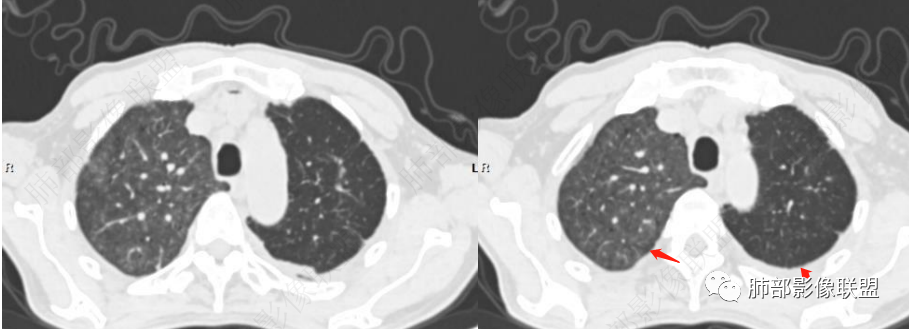

老年男性,胸闷、浮肿10天,左肺尖可见肺大泡影,两肺散在纤维索条影,右肺见弥漫性腺泡结节,以右肺上叶为著,右肺下叶局部小叶间隔增厚,双侧胸腔、右侧叶间裂及心包积液,结合实验室及影像检查,符合心衰及肺水肿表现,右肺部病变符合PVOD表现。

2.右肺广泛密度增高、腺泡结节样磨玻璃影,血管影明显扩张,小叶间隔增厚。

3.右肺下叶纤维钙化灶。

4.左肺相对广泛低密度、血管纤细(显著)。

(1)肺缺血:当肺叶或肺段动脉栓塞时,相应区域内的肺血管影纤细或减少,肺野密度减低。部分患者肺体积缩小。

(2)“马赛克”征:肺内灌注不均匀,表现为正常的肺组织代偿性高灌注与栓塞所致相应肺组织灌注下降相间存在。